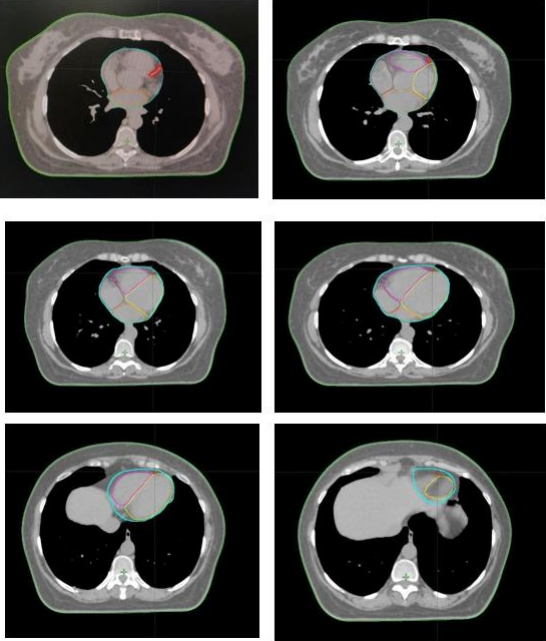

Breast tissue, chest wall, and nodal delineation were contoured according to RTOG guidelines[13]. The Heart & LAD were contoured using a heart atlas. The LAD artery was contoured on the RT planning CT scan (on DIBH scan for 19 patients and on FB scan for 7 patients) immediately distal to its branch-point from the Left Main coronary artery along the anterior interventricular groove to the apex of the Heart using a published contouring atlas [14] [15] [16].

Figure 2: Image showing heart, LAD contour

Figure 3a, Figure 3b

Figure 3: a) LAD CONTOURED AND SPARED, b) LAD CONTOURED BUT NOT SPARED